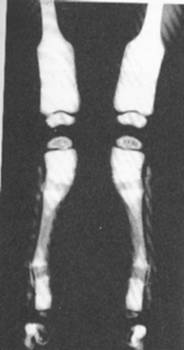

10. Rahitismul

- faza de debut: atingerea osoasa este discreta si intereseaza extremitatile inferioare ale radiusului si ulnei. Marginea metafizara este demineralizata si franjurata, ulterior se largeste si devine concava;

- perioada de stare: -largirea spatiului metafizo-epifizar (marginea metafizara largita si dantelata), -nucleul epifizar de osificare apare tardiv si

Fig. 118 -    Rahitism carential comun

este rarefiat, -afectare diafizara (demineralizare, fracturi in lemn verde), -intarzierea inchiderii fontanelelor si franjurarea contururilor suturale, -deformarea si marirea extremitatii anterioare a coastelor.

- formele severe: - demineralizarea intregului schelet, -deformarea toracelui care devine plat, cu baza largita si sternul proiectat anterior.

- deformarile rahitice: apar in formele severe netratate si constau in: deformari toracice, cifoscolioza toracala, coxa vara bilateral.